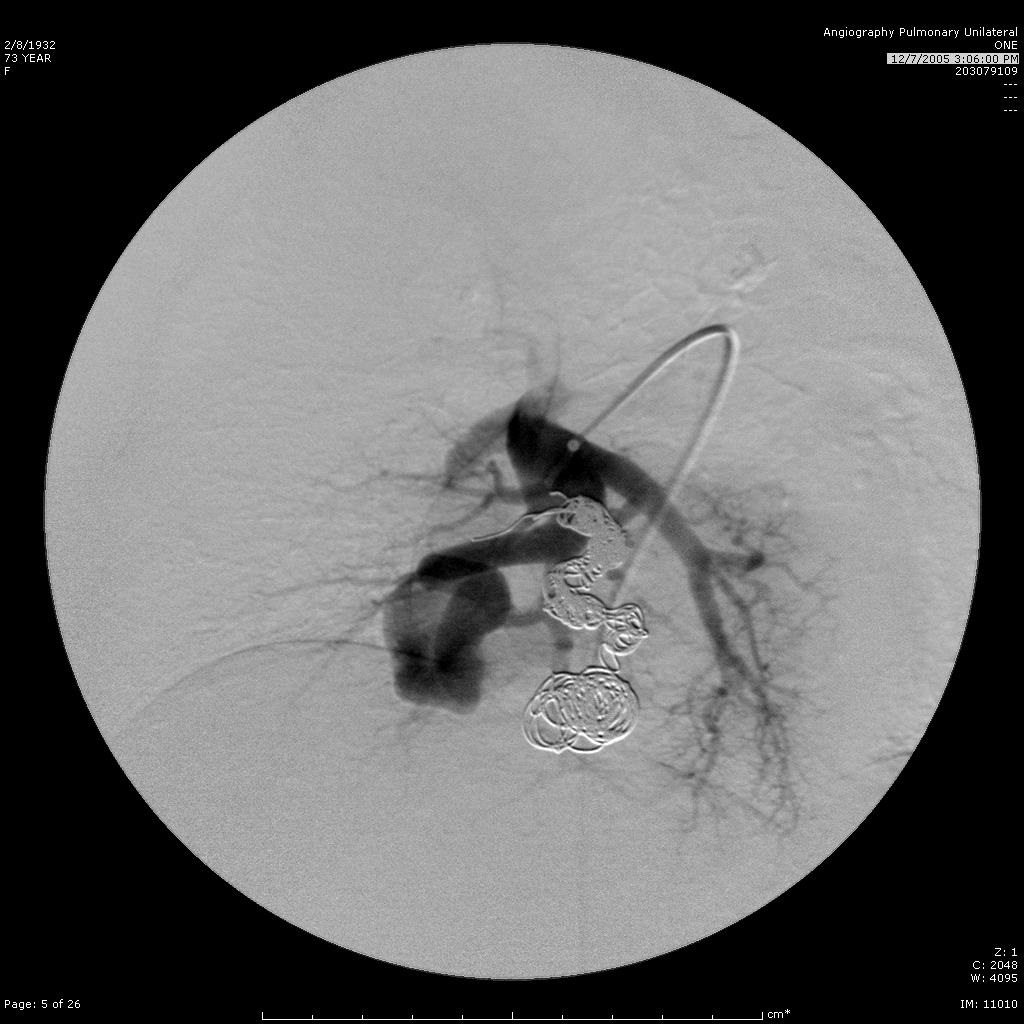

肺动静脉畸形

选择其中一支畸形的滋养动脉 |

造影剂经静脉池回流至肺静脉 |

造影剂经静脉池回流至肺静脉 |

栓塞开始:先致密填塞静脉池,再致密栓塞滋养动脉 |

造影显示部分静脉池不显影,滋养动脉闭塞 |

选择性肺动脉造影显示另一支滋养动脉和静脉池。 |